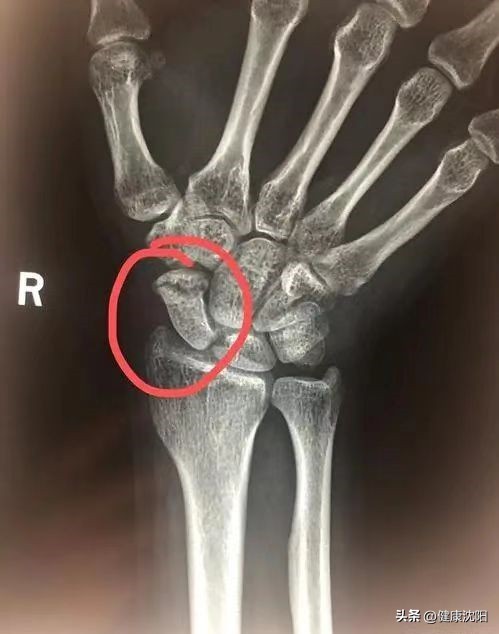

在家属朋友等人陪同下,及时到正规医院就诊,经过专业医生初步诊查,完善CT、X线检查,明确是否存在骨折情况,并在医生的指导下接受治疗。手腕骨折后的紧急处理需要根据骨折时的情况确定。一般手腕骨折都是受到外伤的作用,因此在手腕骨折时也要注意排查有无其他部位的骨折。